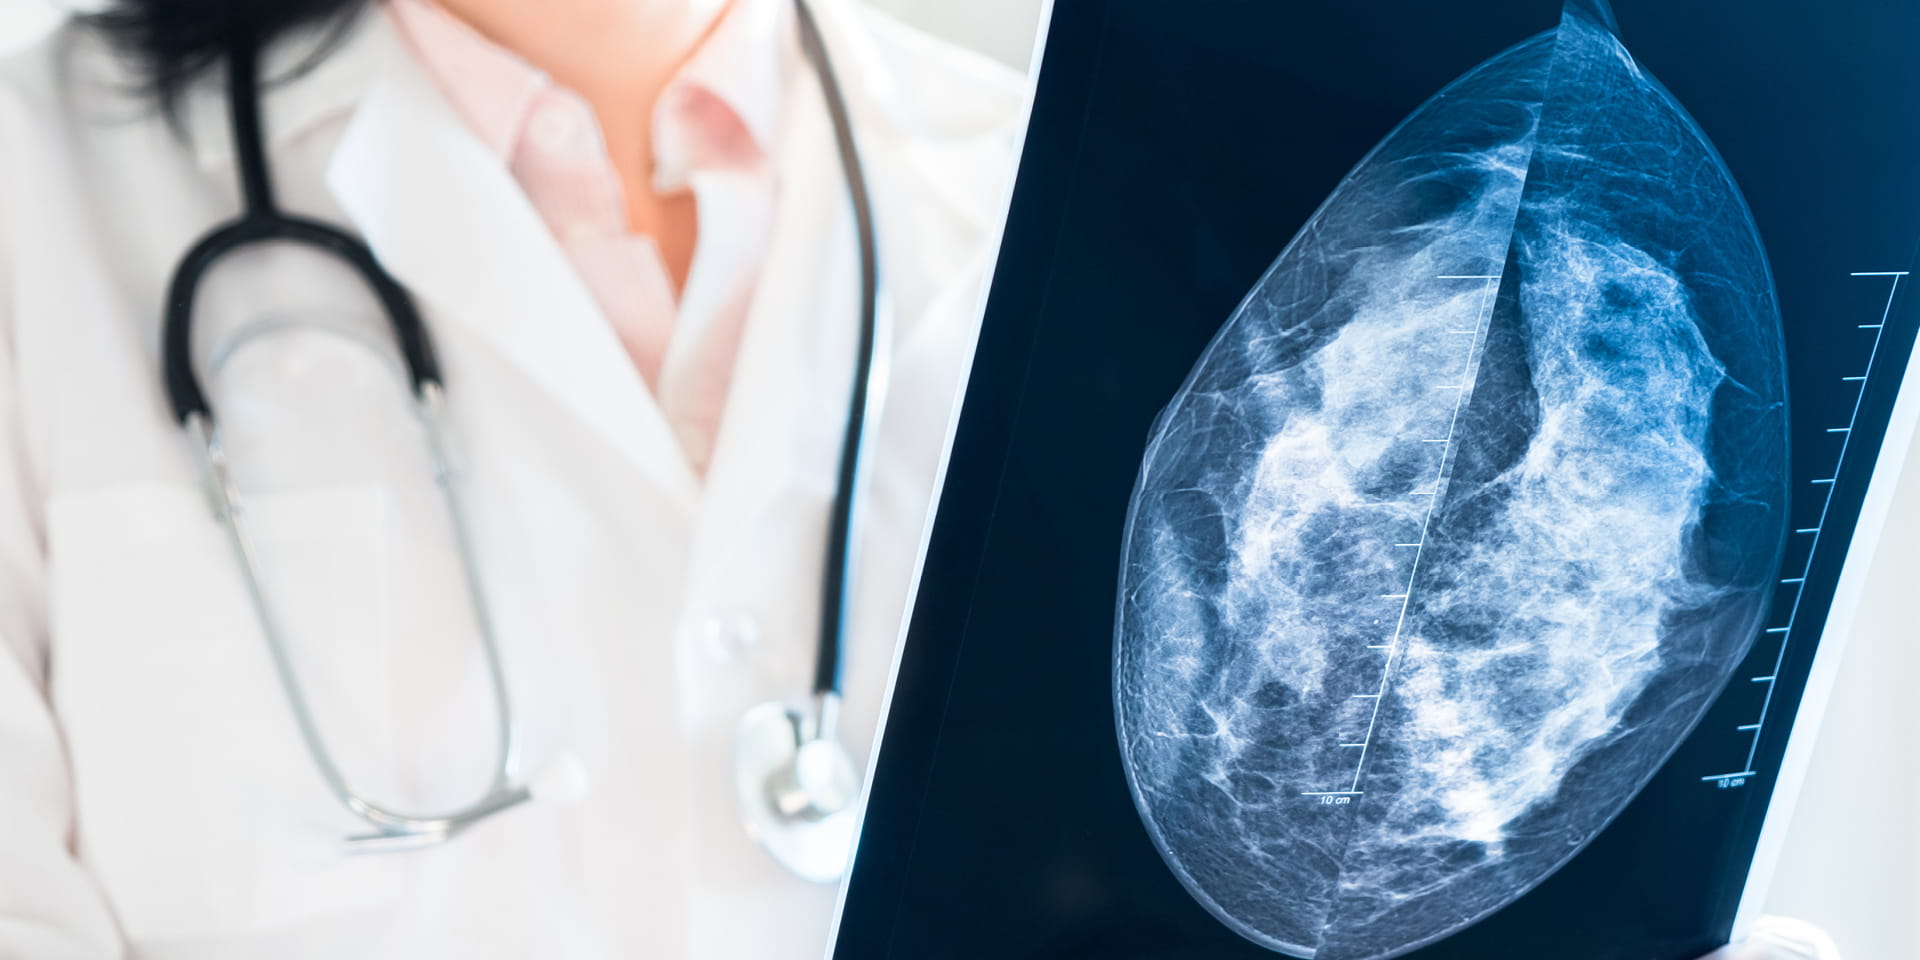

For many years, physicians have used X-ray mammography to detect breast cancer in women and men. Doylestown Hospital offers all-digital mammography that stores an electronic image of the breast as a computer file. This digital information can be magnified or manipulated for further evaluation.

Unlike digital mammography, which produces a 2-dimensional image of the breast, 3D mammography creates a series of images that allows the radiologist to view the breast in multiple, connected slices. This process is similar to how a computed tomography (CT) scanner produces images of various structures inside the body.

It can be more difficult to detect cancer in dense breasts with standard mammography alone. Doylestown Health recommends 3D mammography as the breast cancer screening method for patients who have denser breast tissue and/or a personal history of breast cancer or who carry the gene for breast cancer (BRCA1 or BRCA2).